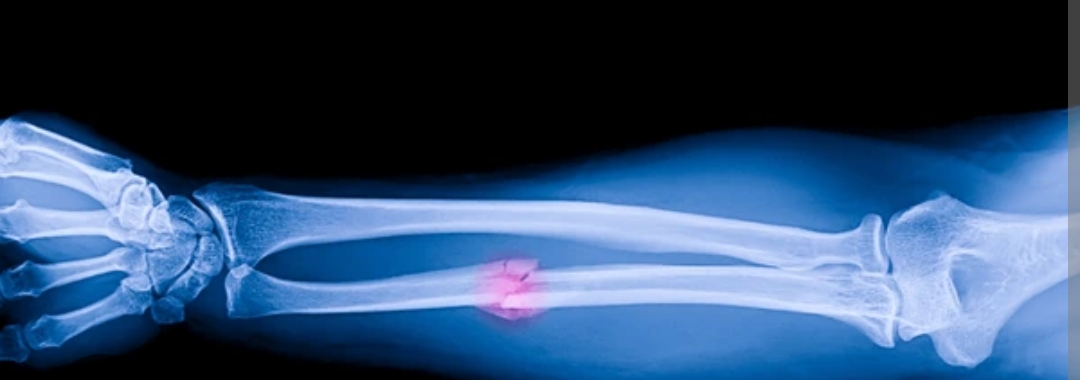

Un grupo de expertos en ortopedia de la provincia de Zhejiang (China) ha desarrollado un pegamento para huesos que es capaz de unir y fijar con precisión fracturas óseas en cuestión de tres minutos y mediante una sola inyección, reporta el portal The China Academy ayer lunes 29 de septiembre del 2025.

Gracias a su tecnología adhesiva, el pegamento, bautizado como Bone 02, ha logrado unir y fijar en unos pocos minutos distintos fragmentos óseos mediante una incisión de 2 a 3 centímetros que resulta mínimamente invasiva.

El material, inspirado en las ostras, representa un avance significativo respecto de los procedimientos tradicionales, que utilizan placas de metal para recuperar los huesos atendidos.